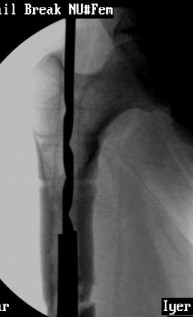

VMI-I am enclosing pictures of how I had to do it once. The C arm picture shows the first attempt to try and jam a solid reamer into the nail and trying to pull it out. Did not work.

The second picture shows a plain guide wire inserted thro the nail, prograde, hammered out thro the distal femur, out thro the skin. A beaded guide wire being railroaded on the earlier G W into the distal end of the nail.

This is the C-arm picture before attemting to pull out thro the proximal end by hammering on a chuck.

Did not work out. The nail was a slotted one. The guidewire split the slot and came out but not the nail. Ultimately as mentioned in an earlier mail, I had to introduce a cannulated nail from distally threadind on the guide wire and hammer on the stuck nail and finally got it out